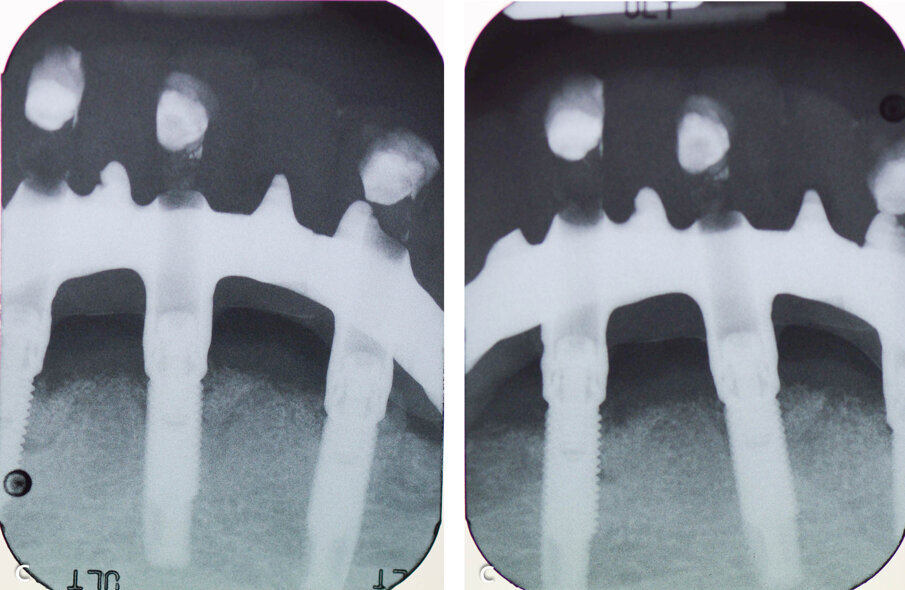

Figure 1. Radiographic assessment at baseline.

Figure 5. Post-op radiographs at 3 months after therapy.

Clinical examination revealed 5 implants in the mandible supporting a fixed full arch reconstruction. Probing pocket depths were of the order of 8-9mm around 3 of the anterior implants. The distal implants had normal probing depths. CBCT imaging revealed an intrabony component of 6.1mm for the implant in the 43 position, 4.2mm at the 41 implant and 3.1 at the 33 implant.